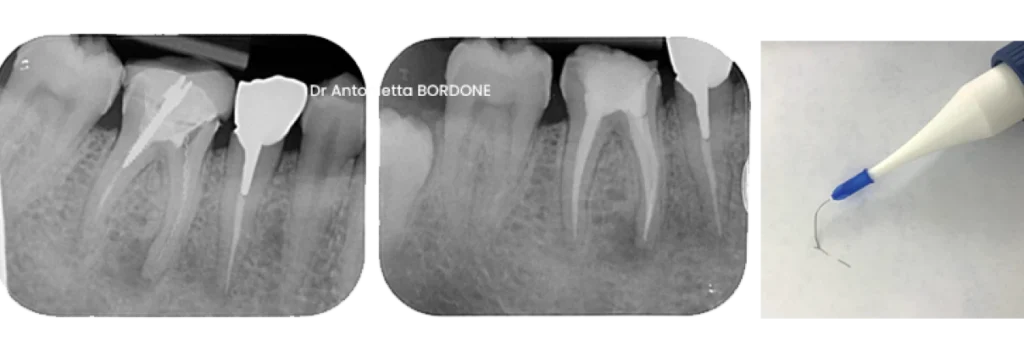

Exemple de retrait d’un instrument fracturé dans un canal avec technique du lasso par le Dr Antonietta Bordone à Marseille

endodontie marseille retrait instrument fracture canal Fracture d’un instrument Dr Antonietta BORDONE - Endodontiste à Marseille

endodontie marseille retrait instrument fracture Fracture d’un instrument Dr Antonietta BORDONE - Endodontiste à Marseille